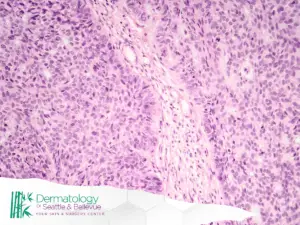

Managing Skin Cancer and Micrographic Surgery

Early detection and expert intervention are key when it comes to skin cancer. Dermatologists in advanced practices often provide:

- Full-body skin exams to catch suspicious lesions early

- Biopsies to confirm or rule out cancer

- Mohs micrographic surgery, a highly precise technique for removing basal cell carcinoma or squamous cell carcinoma

- Ongoing monitoring for high-risk patients

This level of care can help preserve healthy tissue and reduce the risk of recurrence.